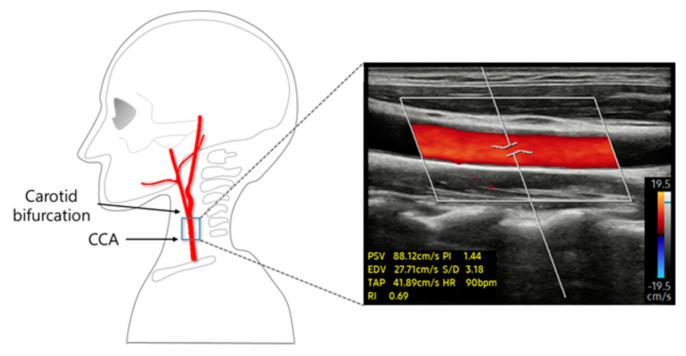

An excessive and abrupt increase in cerebral blood flow may cause blood vessel damage, leading to stroke. Therefore, appropriate methods to immediately regulate blood flow velocity are important. Through an analysis of 31 healthy adults, we therefore investigated whether stimulating the common carotid artery (CCA) using transcutaneous electrical nerve stimulation (TENS) could modulate blood flow velocity in the CCA.

METHODS

Three stimulation intensities (below-threshold, threshold, and above-threshold) were applied in a random order. Blood velocity changes were examined by the measurement of peak systolic velocity (PSV) with Doppler ultrasound before, during, and after TENS stimulation. To evaluate arterial stiffness, pulse wave velocity (PWV) was calculated using CCA diameter, and blood pressure was measured before and after stimulation.